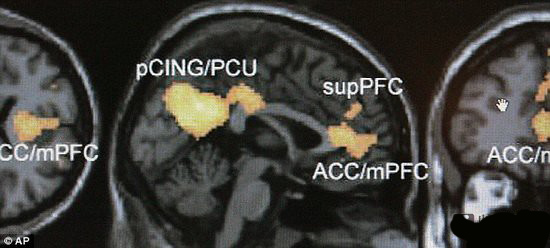

據(jù)英國每日郵報(bào)報(bào)道,目前,科學(xué)家最新研究表明,大腦掃描能夠讓研究人員精確知曉人們大腦想象的事物。這項(xiàng)創(chuàng)新技術(shù)是科學(xué)家使用大腦掃描直接將大腦中的信息譯碼成圖像。

研究人員現(xiàn)在能夠?qū)⑷藗兯吹降臄?shù)字組合在一起,恢復(fù)某人的記憶,以及恢復(fù)某人曾觀看過的視頻。美國康奈爾大學(xué)認(rèn)知神經(jīng)科學(xué)家南森-斯普林格說:“我們?cè)囍斫馊祟惔竽X內(nèi)部世界的物理機(jī)制,同時(shí)能夠呈現(xiàn)人類大腦中其它人物。”

之后測(cè)試者接受功能性磁共振成像掃描,這種技術(shù)通過測(cè)量血流變化來監(jiān)控大腦活動(dòng)性。測(cè)試者被問詢?cè)诓煌瑘?chǎng)景下這些虛擬人物的反應(yīng),例如:如果他們看到一個(gè)無家可歸的老兵乞討錢;或者他們?cè)诰瓢煽吹侥橙送戮啤?

每個(gè)虛擬人物相關(guān)的大腦活動(dòng)狀況都與內(nèi)側(cè)前額葉皮質(zhì)獨(dú)特的大腦活動(dòng)性相關(guān),斯普林格說:“這是首次研究解碼顯示人類大腦所想事物?!?

大腦區(qū)域能夠幫助人們推斷其它虛擬人物的特征,同時(shí),這項(xiàng)研究表明大腦還可以將所想事物進(jìn)行編碼、組合和更新。

這項(xiàng)研究十分重要,證實(shí)了與孤獨(dú)癥和其它社交活動(dòng)抑郁者相關(guān)的大腦區(qū)域,這些患者無法在大腦形成精確的人性化特征,未來伴隨著技術(shù)的更新升級(jí),有望對(duì)這些患者進(jìn)行治療。